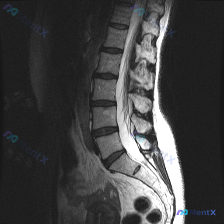

影像来源:腰椎MRI(T2序列,矢状位)

核心影像表现:

- L2/L3、L3/L4、L4/L5椎间盘T2低信号(黑盘征),L5/S1信号也有减低;L4/L5、L5/S1椎间隙略窄,伴椎间盘向后弥漫膨出,硬膜囊前缘受压、变形,相应节段椎管前后径有狭窄

- L4/L5、L5/S1椎体终板边缘可见斑片状高信号

- 腰椎生理前凸变直,各椎体未见明显压缩骨折或明确滑脱

- 后方韧带、竖脊肌信号大致正常

附带的临床讨论点提到了「脊柱侧弯」的可能性,但也指出仅凭这张矢状位MRI无法直接确诊冠状面的侧弯